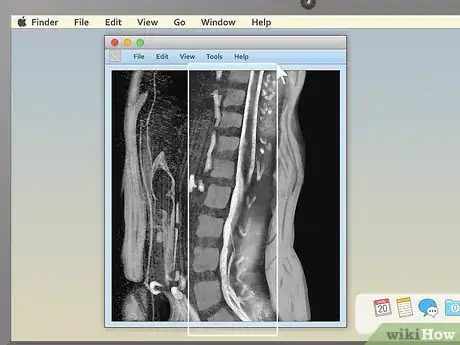

5View the images. Most MRI programs start with a large black space on one side of the screen and a smaller toolbar on the other side. If you see small preview pictures of your MRI images in the toolbar, double click on the image you want to view. It should load a large version of the image into the black area.

1Familiarize yourself with the different MRI viewing schemes. When your MRI first loads up, if you're lucky, it will be immediately obvious what you're looking at. However, in many cases, the image you see may be a completely unintelligible mix of black, white, and grey. Knowing how MRIs are shot can help you make sense of your images. The three main ways MRIs are displayed are:[4]

- Sagittal: Often the easiest for non-doctors to interpret. Sagittal MRIs are basically side or profile views of your body. The image is as if you've been sliced in half vertically, from your head to your pelvis.

- Coronal: These images are basically a "head on" view of your body. You're looking at your features vertically from the front — as if you were standing facing the camera.

- Cross-sectional: Often the hardest for non-doctors to interpret. Here, you're basically viewing thin slices of your body from the top down — as if you've been cut into many thin horizontal slices from your head to your toes like a salami.

3Pick an appealing series layout. MRI programs almost always have the ability to display more than one image at once. This makes it convenient for doctors to compare different views of the same area or even MRIs taken at different times. For most non-doctors, it's easiest to simply choose a one-image-at-a-time layout and cycle through the images individually. However, there should be onscreen instructions to show two, four, or many more images at once, so feel free to play around with this feature.

2Examine the structure of the vertebrae for spinal MRIs. MRIs of the spine are typically some of the easiest for non-doctors to read (especially in sagittal view). Look for noticeable misalignments in the vertebrae or fluid discs. Having just one of either be out of alignment (as in the example above) can be the source of serious pain.

- Behind the spinal vertebrae, in sagittal view, you'll see a white, rope-like structure. This is the spinal cord, the structure connected to all the body's nerves. Look for spots where the vertebrae or discs seem to "pinch" or press into the spinal cord — because the nerves are so sensitive, just a little pressure can lead to pain.